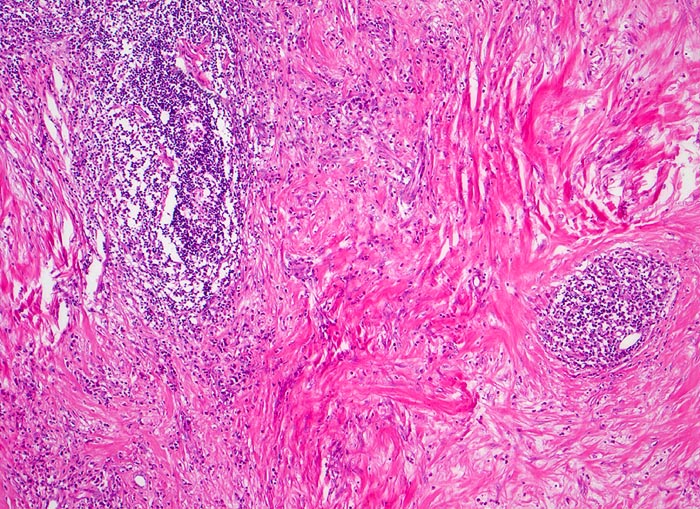

AP/ Klassisches Hodgkin-Lymphom, noduläre Sklerose

Klassisches Hodgkin-Lymphom, noduläre Sklerose

Histologisch charakteristisch für diesen Subtyp sind Sklerose, noduläres Wachstumsmuster und Lakunarzellen. Bei der nodulären Sklerose können Grad I und Grad II (15-25%) Lymphome unterschieden werden; unter modernen Therapiekonzepten allerdings ohne prognostische Bedeutung

• Zerstörung der Lymphknotenarchitektur.

• Von breiten Bindegewebssträngen abgegrenzte Knoten.

• Die Knoten bestehen vorwiegend aus einem Mischzellinfiltrat reaktiver Zellen: Lymphozyten, Histiozyten, eosinophile Granulozyten und Plasmazellen.

• Reed-Sternbergzelle mit spiegelbildlich angeordneten Kernen mit sehr grossen eosinophilen Nukleolen.

• Einkernige Hodgkinzelle mit prominentem Nukleolus umgeben von einem Retraktionsartefakt (Lakunarzelle).